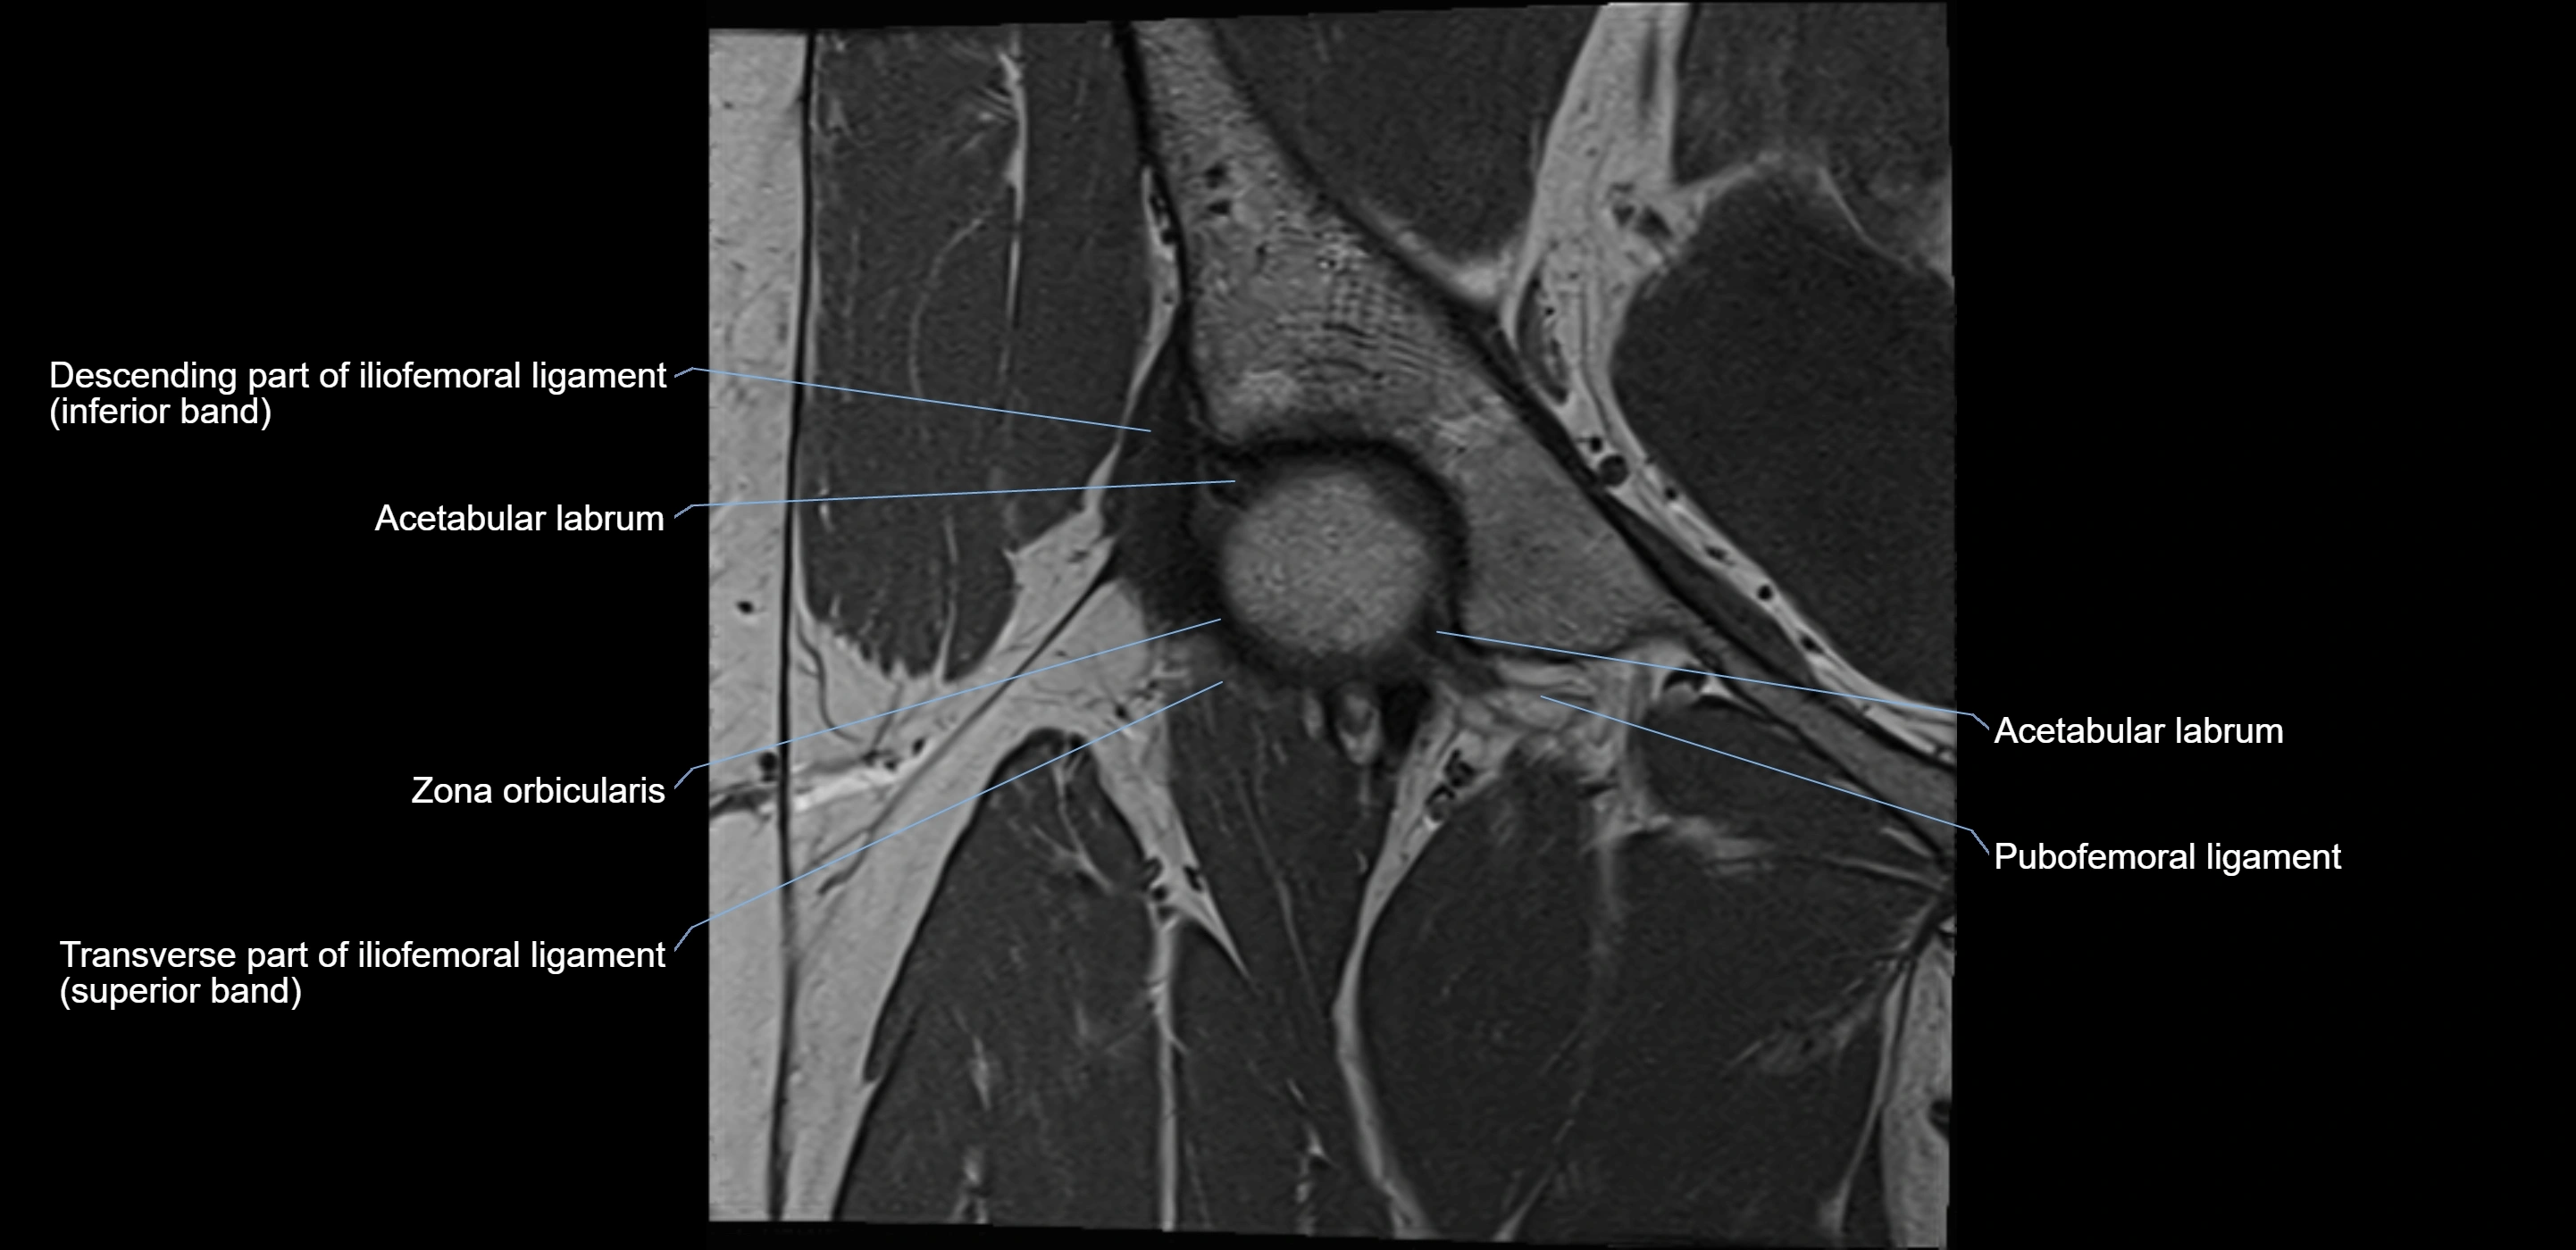

MRI Appearance

T1-weighted images:

• Labrum: low signal intensity (dark)

• Surrounded by intermediate signal joint fluid (bright on arthrogram)

• Tears: linear or focal areas of intermediate-to-high signal interrupting labral continuity

T2-weighted images:

• Joint fluid: bright, making labral tears visible as fluid extending into or around labrum

• Degeneration: may show areas of increased signal within labrum

MRI image

image